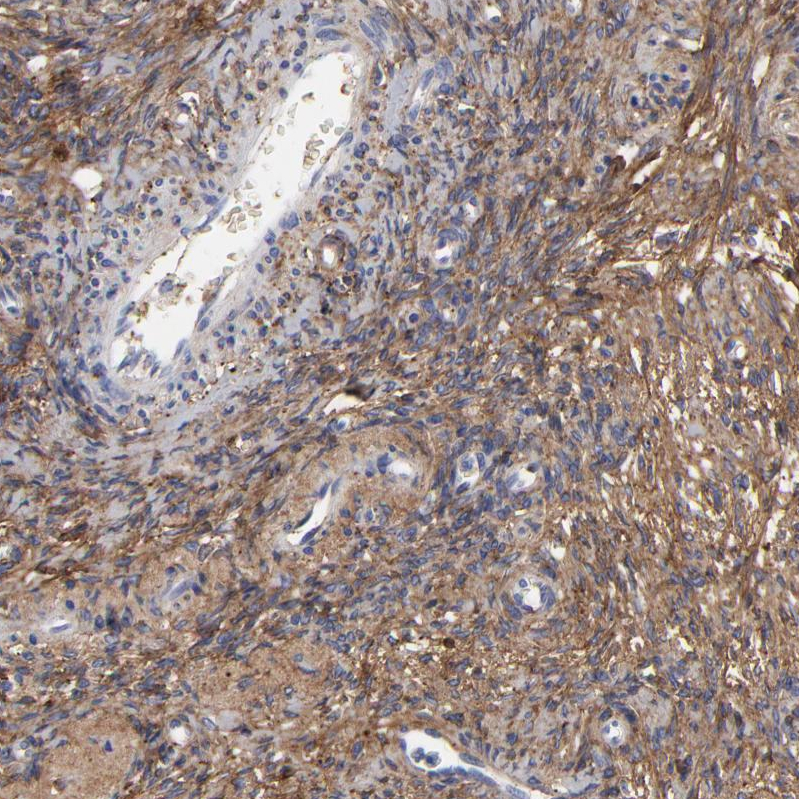

Immunohistochemical staining of human ovary shows moderate cytoplasmic positivity in stromal cells.